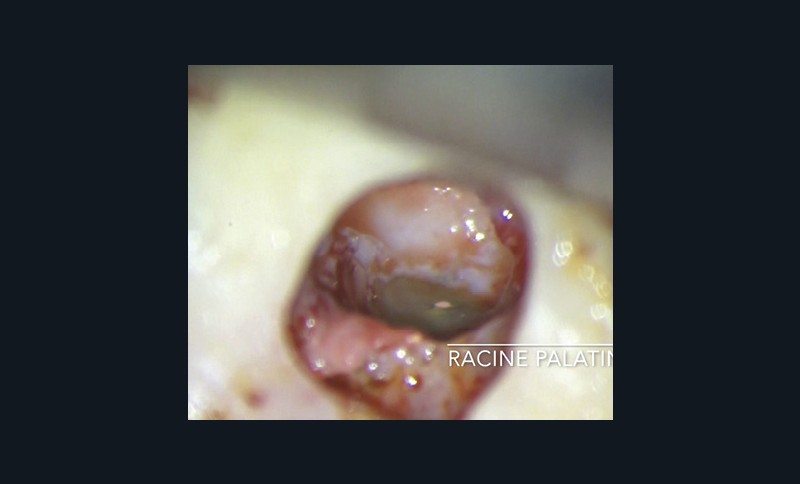

Chirurgie endodontique

L’Er:YAG a également sa place en chirurgie endodontique. En mode ablatif, il permettra l’élimination des tissus de granulation et des tissus fibro-kystiques en assurant la stérilisation de la crypte osseuse ainsi formée.

La résection apicale et la préparation a retro exposent des canaux et des tubulis dentinaires infectés, qui pourront là aussi, être décontaminés par l’action du laser Er:YAG et de l’eau distillée [36].

Les espaces non accessibles à l’instrumentation conventionnelle pourront, là aussi, être débridés et stérilisés (fig. 11a à f). Cette procédure semble accélérer de manière très significative les processus de régénération osseuse (fig. 11f).

Le laser Er:YAG permet de stériliser la partie apicale du canal, après l’avoir préparée a retro, ainsi que les tubulis dentinaires contaminés exposés.

Enfin, pendant la prise du matériau, le laser Er:YAG permet de pulvériser la lésion fibro-kystique et les tissus inflammatoires avant la réimplantation de la dent dans son alvéole ainsi stérilisée. Nous utilisons alors son mode photo ablatif décrit précédemment (fig. 12a à f).